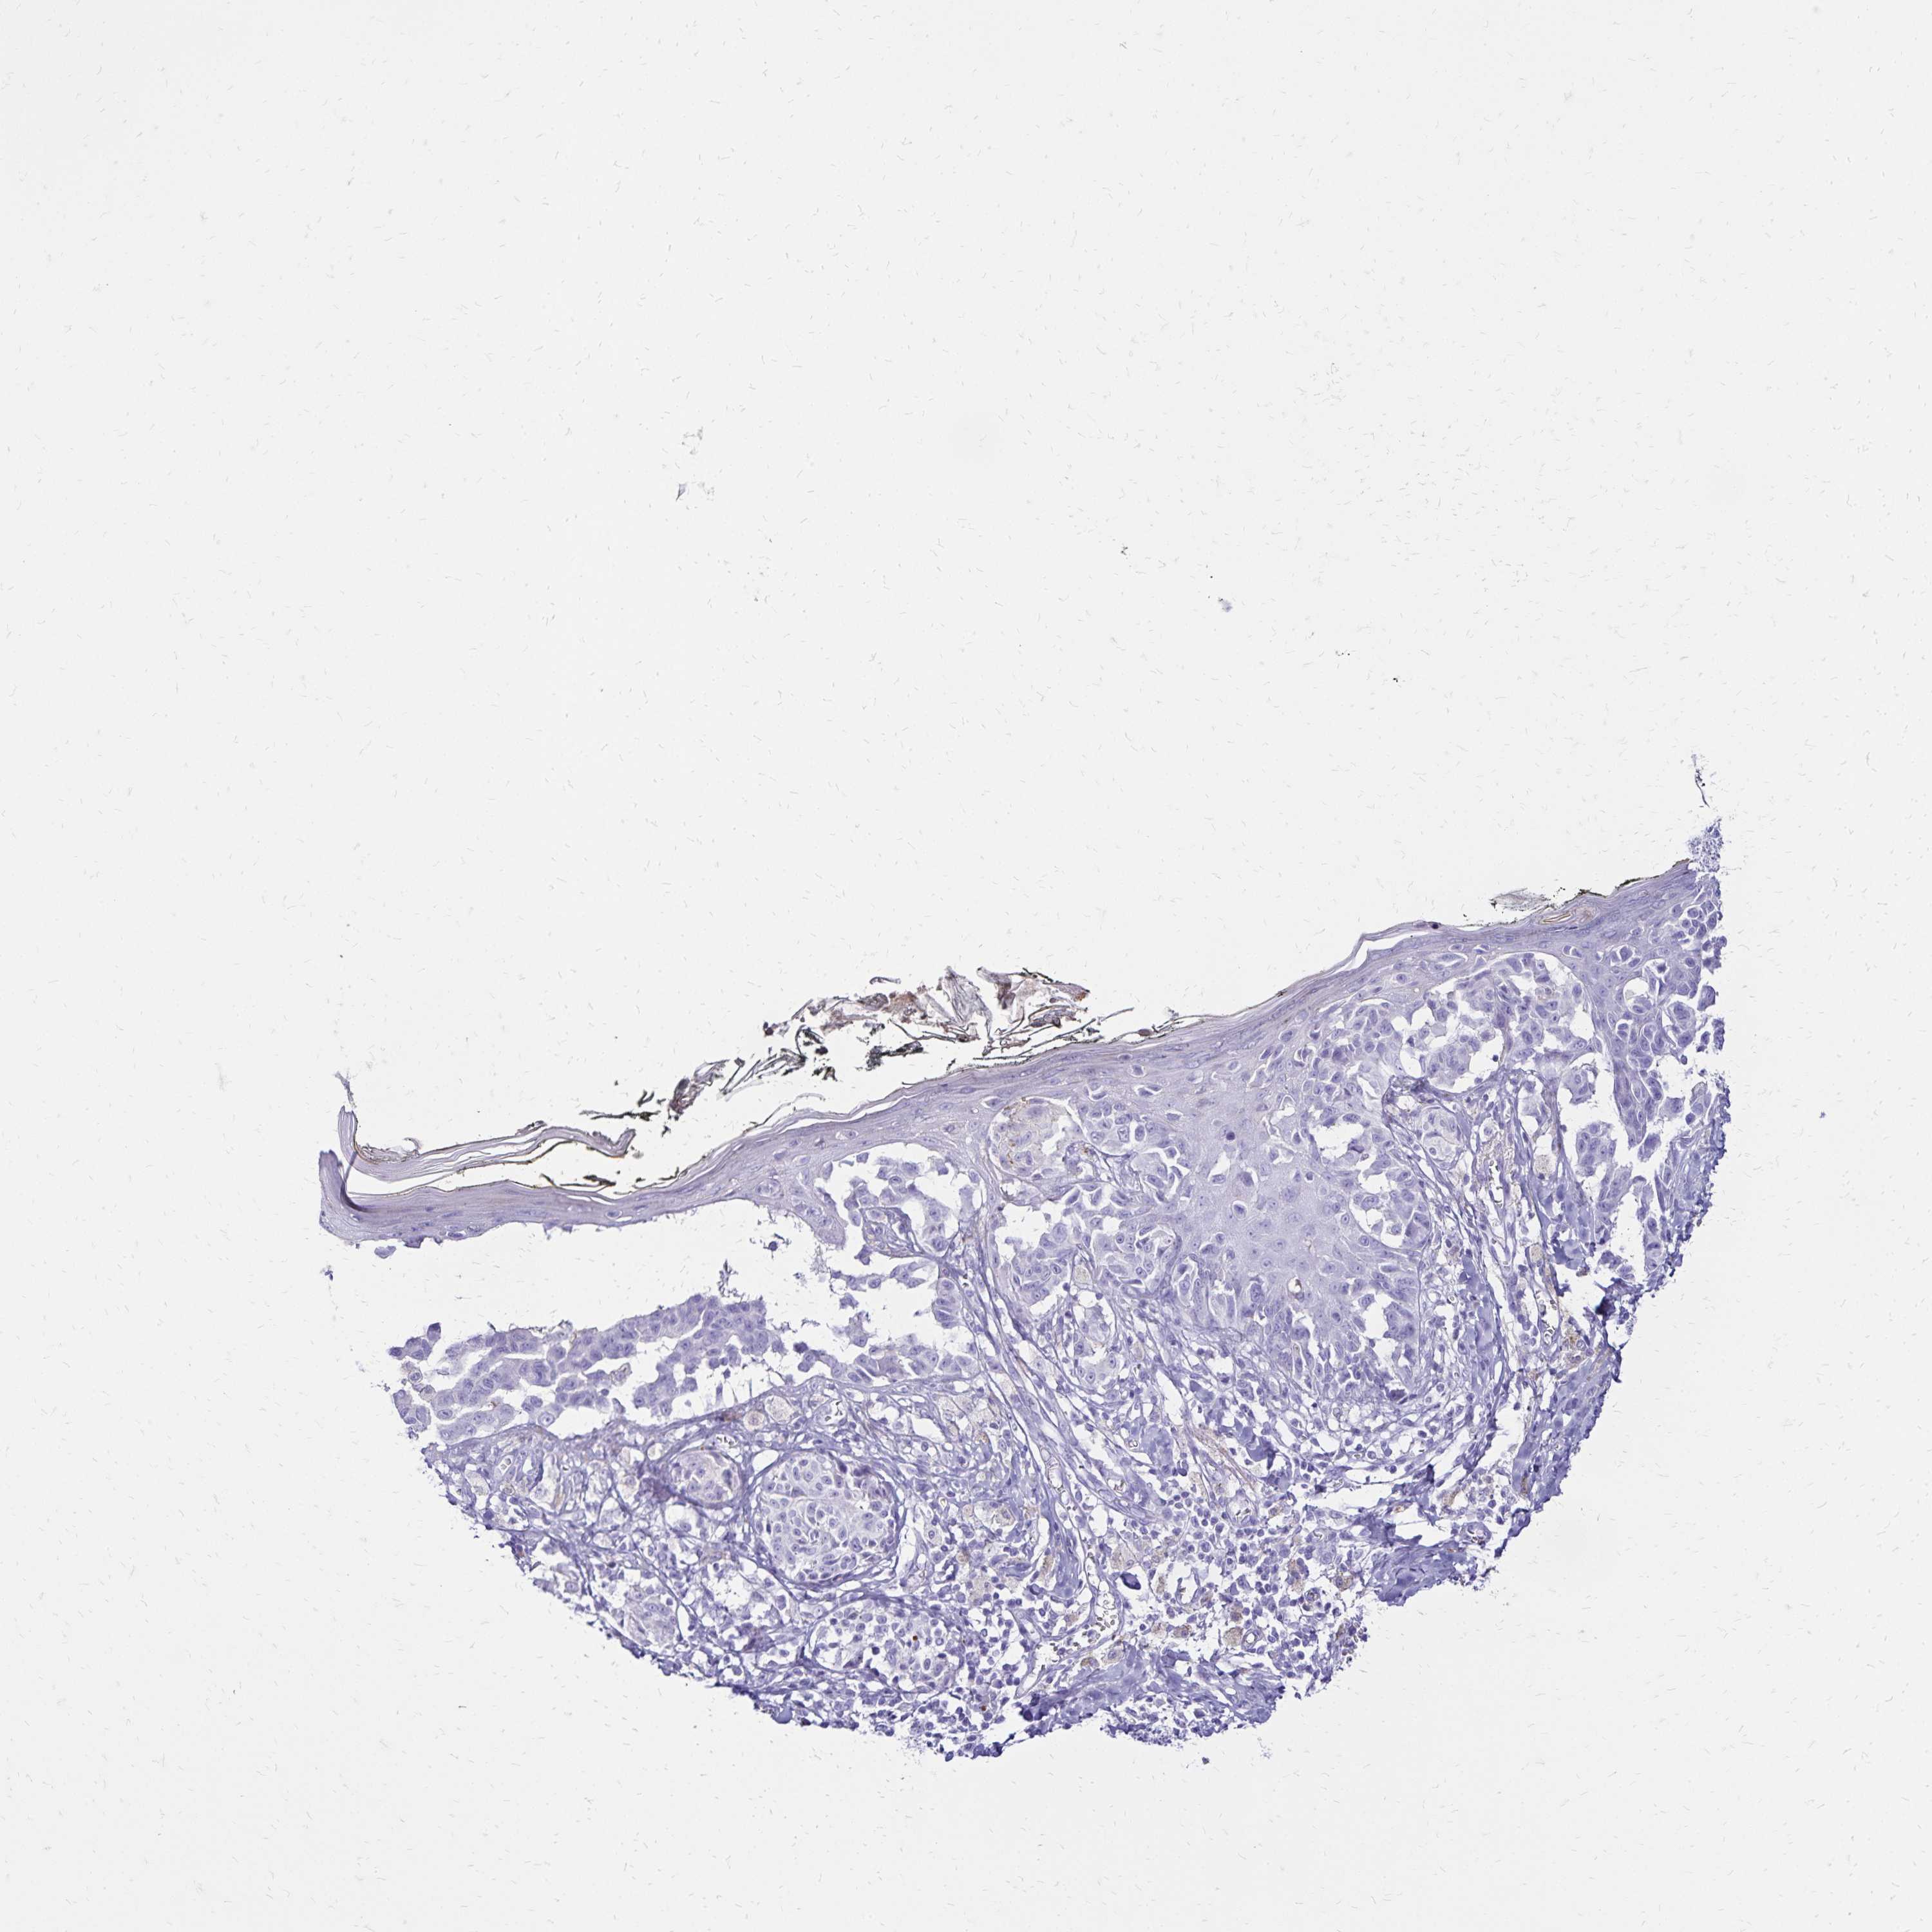

MELANOMA - Protein expressioni

A mouse-over function shows sample information and annotation data. Click on an image to view it in a full screen mode. Samples can be filtered based on level of antibody staining by selecting one or several of the following categories: high, medium, low and not detected. The assay and annotation is described here.

Note that samples used for immunohistochemistry by the Human Protein Atlas do not correspond to samples in the TCGA dataset.

Antibody stainingi

Antibody staining in the annotated cell types in the current human tissue is reported as not detected, low, medium, or high, based on conventional immunohistochemistry profiling in selected tissues. This score is based on the combination of the staining intensity and fraction of stained cells.

Each image is clickable and will lead to virtual microscopy that enables deeper exploration of all samples and also displays staining intensity scores, fraction scores and subcellular localization as well as patient and tissue information for each sample.

Antibody HPA035363

Antibody HPA035364

Malignant melanoma, NOS

Malignant melanoma, Metastatic site